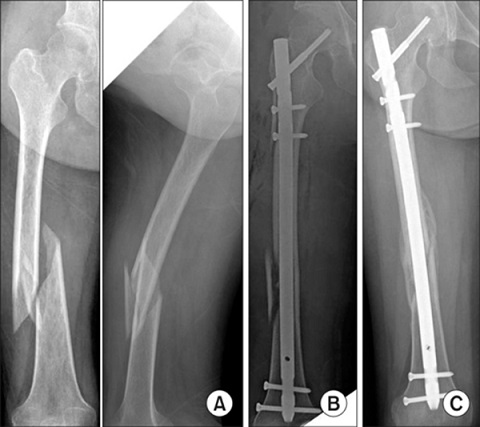

4- درمان شکستگی تنه ی استخوان ران: امروزه تقریبا تمامی شکستگی های ران بالغین با عمل جراحی درمان میشوند. روش کار بدین صورت است که ابتدا شکستگی ران بصورت بسته جااندازی میشود (با استفاده از کشش و مانورهای مخصوصی سعی میشود شکستگی بصورت بسته جااندازی شود. این جااندازی در اطاق عمل انجام شده و پزشک جراح مراحل جااندازی را با استفاده از رادیوگرافی بخصوصی که تصاویر آن مستقیما بر روی مانیتور قابل دیدن است - فلوروسکوپی- کنترل میکند). سپس از راه شکاف های کوچکی که در پوست داده میشود میله داخل استخوانی یا پلاک یا اکسترنال فیکساتور به استخوان متصل شده و آنرا فیکس میکند. به این روش جااندازی بسته و فیکساسیون داخلی یا خارجی میگویند. در صورتیکه جااندازی بسته امکانپذیر نشود پزشک جراح از جااندازی باز استفاده کرده و سپس با روش های پلاک گذاری یا میله گذاری اینترامدولاری شکستگی را فیکس و بی حرکت میکند.